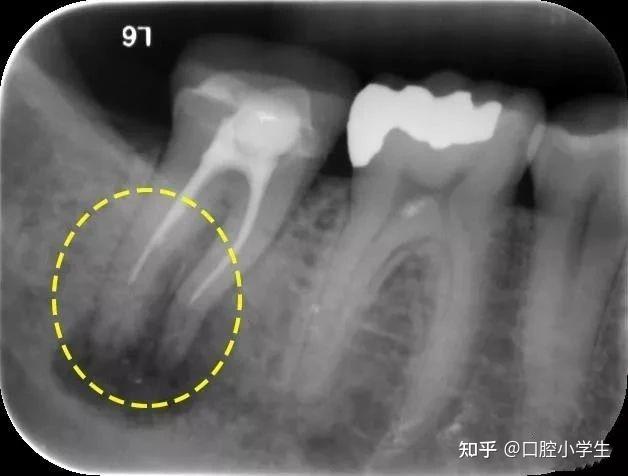

【求助】根充两月后疼痛